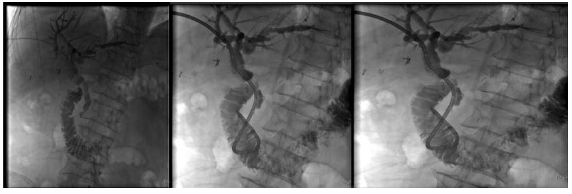

Doppler ultrasonography allowed diagnoses of biliary dilatation in 12 LT patients with bile stones. Five patients with normal ultrasonography findings had intrahepatic dilatation and filling defect in the major bile duct diagnosed by magnetic resonance cholangiopancreatography, and one patient was diagnosed by interventional radiology. Nine patients with bile stones had endoscopic retrograde cholangiopancreatography first, with 5 of these patients having a successful procedure (Figure 1). The remaining 4 patients required bile duct casts and stones cleared by percutaneous transhepatic cholangiography (basket catheter or balloon dilatations) (Figure 2). The percutaneous transhepatic cholangiography procedures were repeated in 10 patients every 3 weeks. With these treatments, all patients recovered, showing normal radiologic, clinical, and laboratory findings. One patient lost graft function as a result of recurrent biliary complications and cholangitis. No patients died as a result of bile stones.

Figure 1. Bile Stones After Liver Transplant Treated With Endoscopic Retrograde Cholangiopancreatography